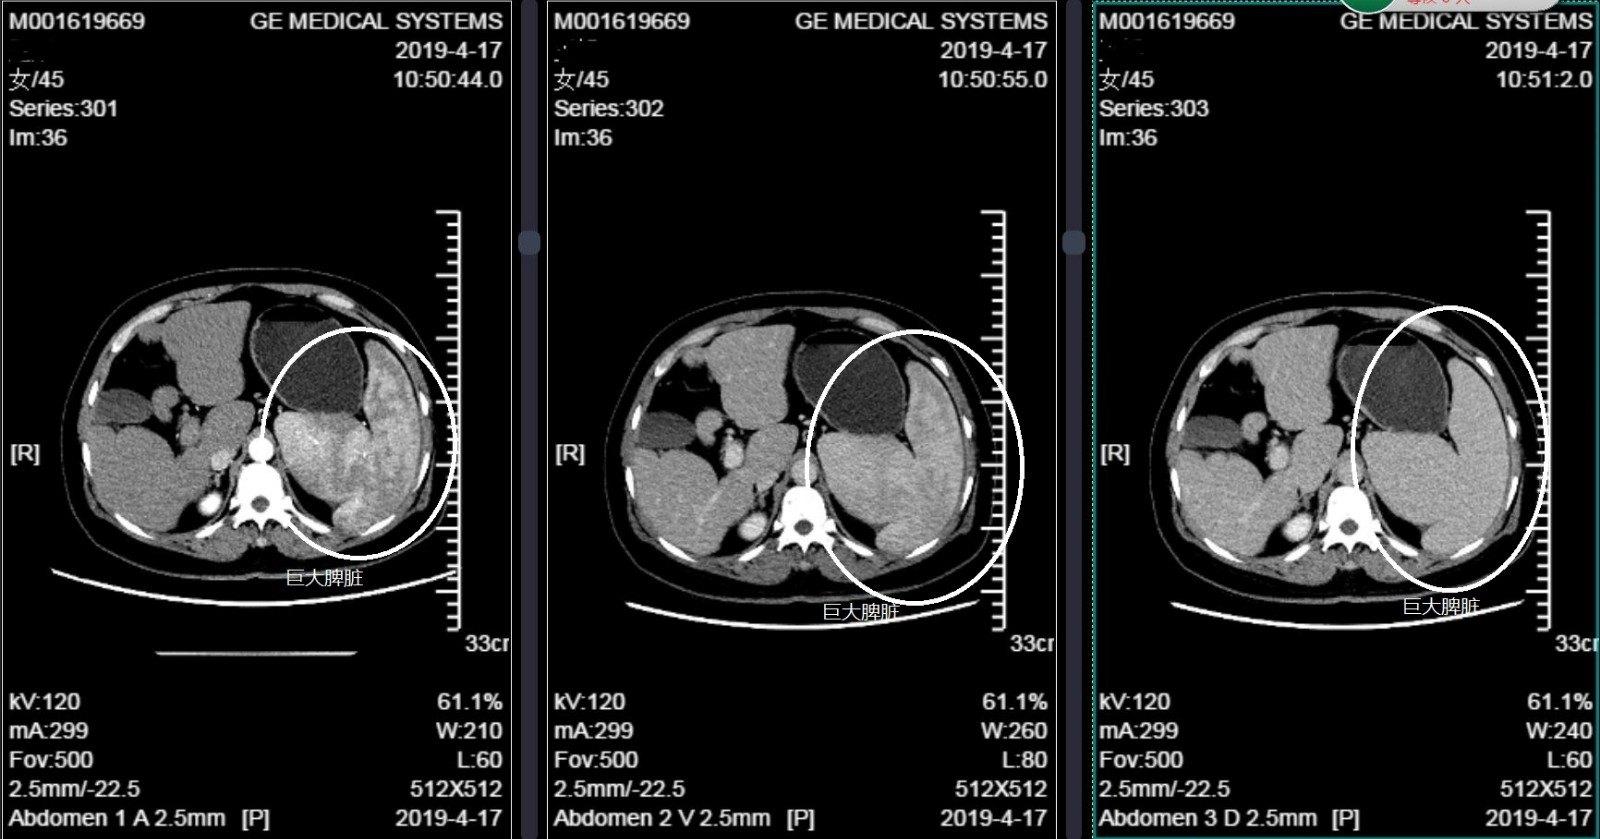

增强ct显示脾大,正常人脾脏约400g,而该患者的脾脏接近8-10斤,是一个